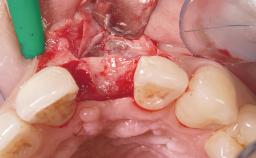

Late Placement of an Implant in a Maxillary Left Central Incisor Site

A 36-year-old female patient was referred for the replacement of the upper left central incisor (tooth 21), which had fractured. Although the tooth had been asymptomatic for many years, the crown began to loosen, at which time she presented to her dentist for an assessment. Teeth 21 and 22 had both been endodontically treated many years previously. She was a healthy individual and a non-smoker.

The crown of tooth 21 was splinted to the adjacent teeth with composite resin, and the gingiva was inflamed.